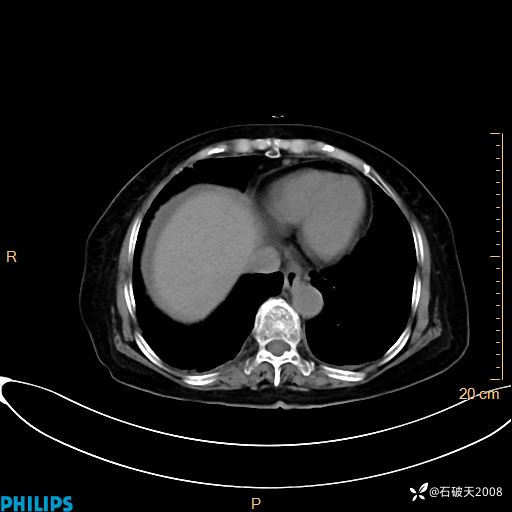

平扫